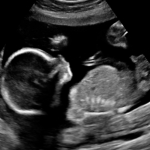

Okay from our scan at 20w 5d. Tech did not reveal gender (and DH covered my eyes when she said she was measuring the legs!). But I was flipping through our pictures and have a shot that has me wondering. So here are the pics. Suspicious shot is the last

Here's the shot that has me wondering. What do you think?

I agree, very suspicious

Hmmmm I'm no ultrasound wizz but is that a peepee? X

You posted it so I'm saying it- that's a boy!

Thats probably the most suspicious shot I've ever seen lol!! I wonder how long that envelope is gonna stay closed